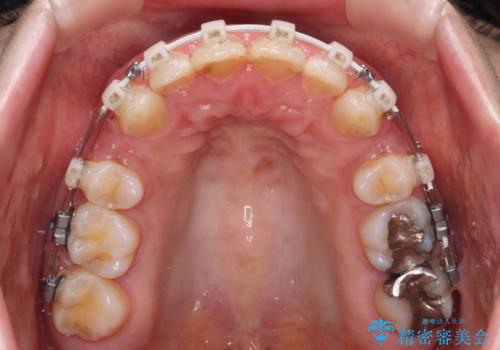

- 矯正装置

- 審美装置

骨格的に上顎が前方にあり、上顎のみの抜歯矯正のため、期間はかかることが予想されましたが、スムーズに移動してくれたおかげで、2年弱の短期間で終えることができました。